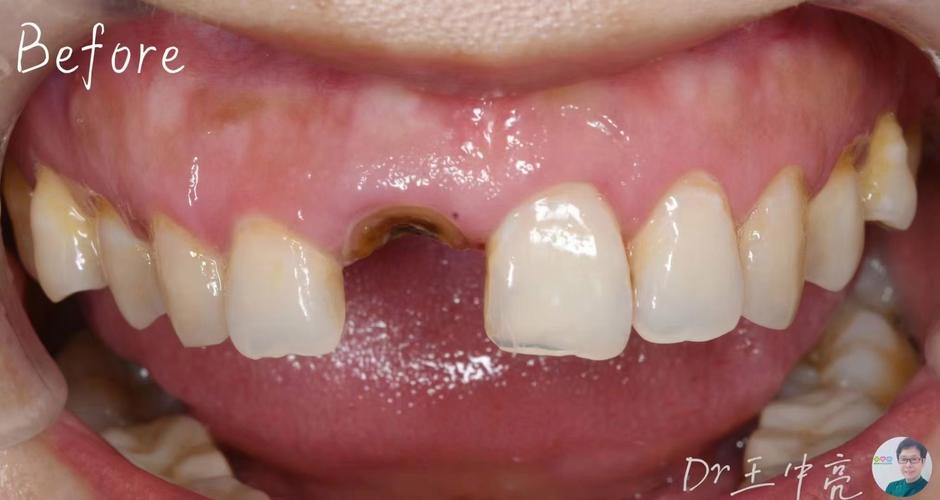

种植体周围炎:

(图片来源网络,侵删)- 症状:牙龈红肿、出血、溢脓、种植体松动、牙龈萎缩。

- 原因:口腔卫生不佳、咬合力过大、吸烟等导致细菌感染,破坏骨结合。

- 处理:需立即进行专业治疗(清创、抗菌药物、骨增量等),否则可能导致种植体脱落。